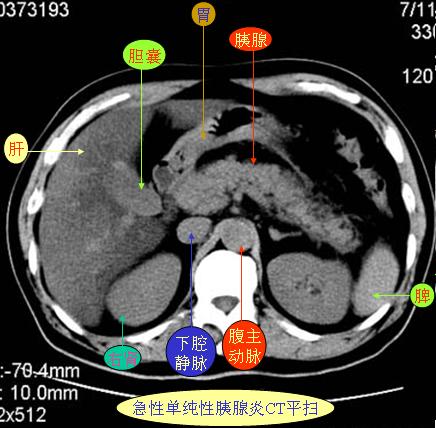

腹部ct解剖与基本病变